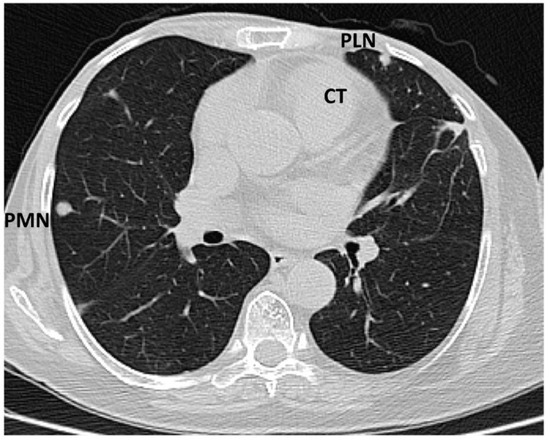

The tumour size and degree of infiltration over the whole apex of the left ventricle were determined by injecting 2 mL of SonoVue (Bracco S.p.A., Milan, Italy) at the level of intra-myocardial contrast in the left ventricle. The presence of microbubbles at this level confirmed the vascularization of the tumour mass. A non-homogeneous right ventricular mass of 88/61/80 mm extending to the left ventricle with areas of necrosis in both ventricles, disseminated lobular nodules on both pulmonary fields measuring 9 mm (right lung), 17 mm (left lung), and right para-tracheal adenopathy were identified on a thoracic CT scan (Figure 5 and Figure 6).

Figure 5. Computed tomography scan: sub-pleural peripheral nodular lesions typical of tumours (abbreviations: CT = cardiac tumour, PLN = pleural nodule, PMN = pulmonary nodule).

Diagnostics 14 00919 g005

Figure 6. Computed tomography scan: parietal tumour thickening at the level of the apex of the heart predominantly in the left ventricle, slightly).

Diagnostics 14 00919 g006